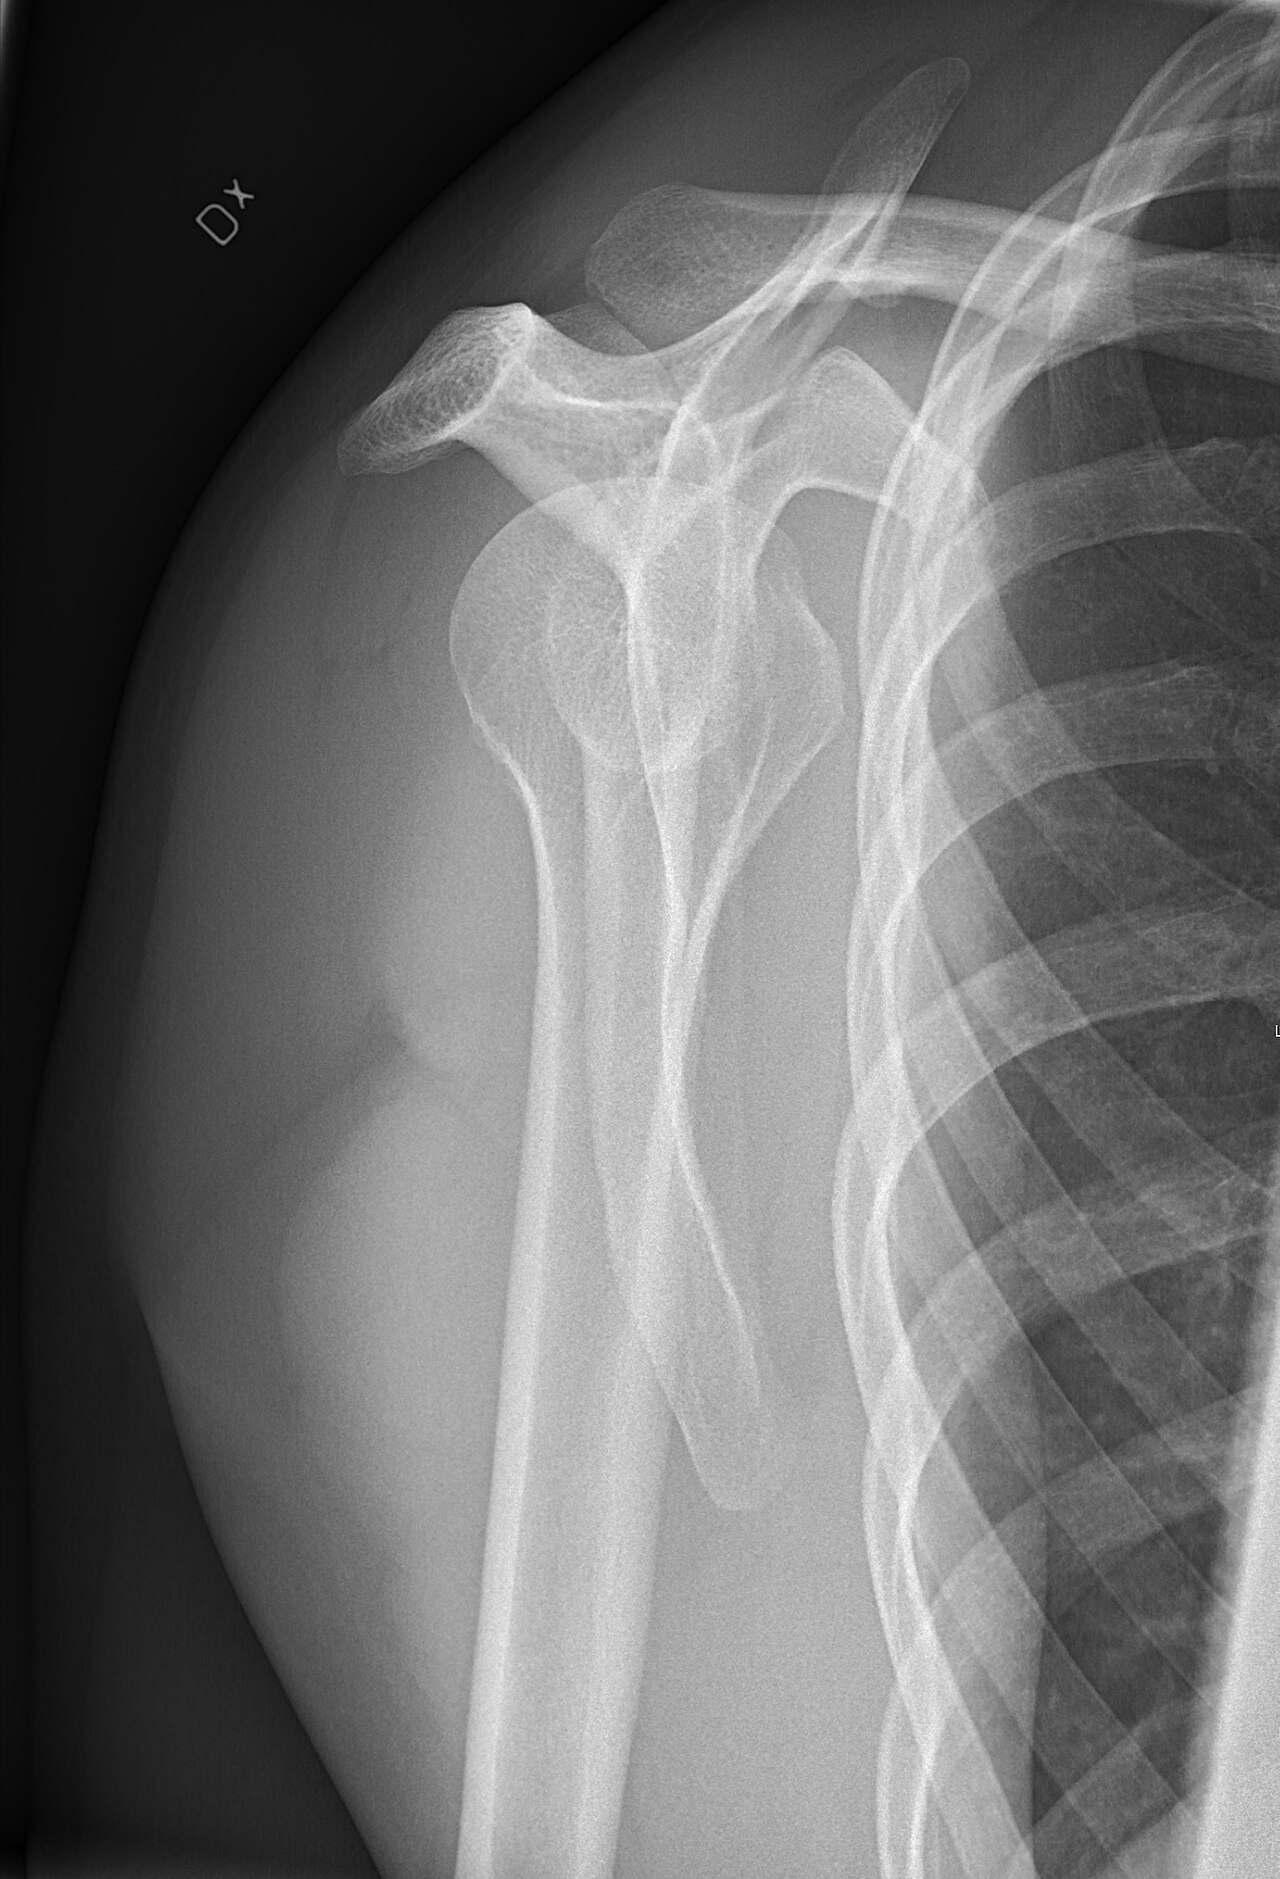

Shoulder phantom with humeral head, glenoid, rotator cuff tendons, labrum, and biceps tendon